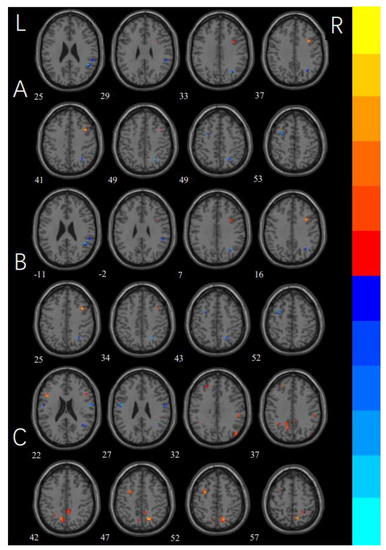

3.4. Functional Connectivity

| MNI x, y, z | Voxels | T Values | Side | Brain Region | |

|---|---|---|---|---|---|

| Checker > Washers | |||||

| CL1 | 36, 12, 39 | 20 | 5.1965 | R | middle frontal gyrus |

| Checker < Washers | |||||

| CL1 | 48, −81, −9 | 12 | −4.1982 | R | inferior occipital gyrus |

| CL2 | 54, −39, 27 | 13 | −4.5237 | R | supramarginal gyrus |

| CL3 | 24, −60, 45 | 11 | −5.0666 | R | angular gyrus |

| CL4 | −30, 3, 51 | 15 | −5.0536 | L | middle frontal gyrus |

| Checkers > HCs | |||||

| CL1 | 0, −75, −24 | 16 | 4.7627 | R | vermis |

| CL2 | 9, 66, −12 | 10 | 4.4357 | R | medial orbital frontal gyrus |

| CL3 | 15, −48, 15 | 13 | 5.0067 | R | precuneus |

| CL4 | −39, −69, 24 | 19 | 5.8556 | L | middle occipital gyrus |

| CL5 | −9, 36, 39 | 41 | 4.9037 | L | medial superior frontal gyrus |

| CL6 | −42, −60, 36 | 13 | 4.2971 | L | angular gyrus |

| CL7 | −12, −60, 42 | 13 | 4.9284 | L | precuneus |

| CL8 | 21, 18, 42 | 18 | 5.2585 | R | superior frontal gyrus |

| CL9 | −27, −45, 48 | 11 | 4.9786 | L | inferior parietal gyrus |

| CL10 | −9, 6, 51 | 33 | 5.1527 | L | supplementary motor area |

| Checkers < HCs | |||||

| CL1 | −48, −27, −3 | 12 | −4.885 | L | middle temporal gyrus |

| CL2 | −48, −75, −6 | 19 | −4.1681 | L | middle occipital gyrus |

| CL3 | 45, −69, 6 | 15 | −4.0421 | R | middle temporal gyrus |

| CL4 | 51, −21, 54 | 17 | −4.7041 | R | postcentral gyrus |

| CL5 | 39, −12, 57 | 16 | −4.4824 | R | precentral gyrus |

| Washers > HCs | |||||

| CL1 | −45, 15, 18 | 14 | 5.8462 | L | inferior frontal gyrus |

| CL2 | 51, −30, 33 | 10 | 4.1435 | R | supramarginal gyrus |

| CL3 | −27, −51, 39 | 10 | 4.6492 | L | inferior parietal gyrus |

| CL4 | −12, −60, 39 | 39 | 5.1497 | L | precuneus |

| CL5 | 6, −45, 42 | 25 | 4.1893 | R | precuneus |

| CL6 | 18, −63, 48 | 23 | 5.6277 | R | precuneus |

| CL7 | −30, 3, 51 | 19 | 5.3576 | L | middle frontal gyrus |

| Washers < HCs | |||||

| CL1 | 57, −6, 24 | 21 | −4.2078 | R | postcentral gyrus |

| CL2 | −51, −6, 24 | 10 | −4.2393 | L | postcentral gyrus |